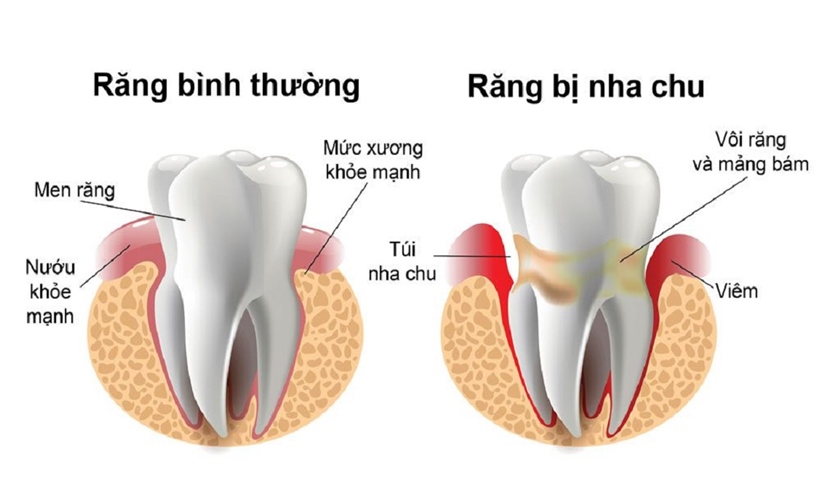

Nướu là phần mô lợi bao bọc phía quanh răng, góp phần giữ cho cấu trúc của răng chắc khỏe. Nướu răng kết hợp với dây chằng răng và xương ổ răng tạo thành một thể nâng đỡ răng thống nhất. Khi nướu bị ảnh hưởng thì các bộ phận còn lại cũng theo đó mà có những triệu chứng suy yếu.

Bệnh viêm nướu là tình trạng viêm nhiễm của nướu với biểu hiện đặc trưng của viêm là sưng, nóng, đỏ, đau. Đây là giai đoạn đầu trong chuỗi triệu chứng của bệnh viêm nha chu nguy hiểm. Cần phát hiện sớm, điều trị kịp thời và đặc biệt quan trọng là tránh tái phát viêm nướu răng để bệnh không tiến triển thành viêm nha chu

Răng lung lay

Tiêu huỷ mô xương và nướu răng do bệnh nha chu sẽ khiến răng lung lay. Vì các mô bị tổn hại, nên nướu răng không còn ôm sát chân răng, dễ làm răng bị lung lay. Và răng lung lay sẽ làm cho khoảng cách giữa các răng lớn dần, nặng hơn sẽ dẫn đến tình trạng mất răng vĩnh viễn